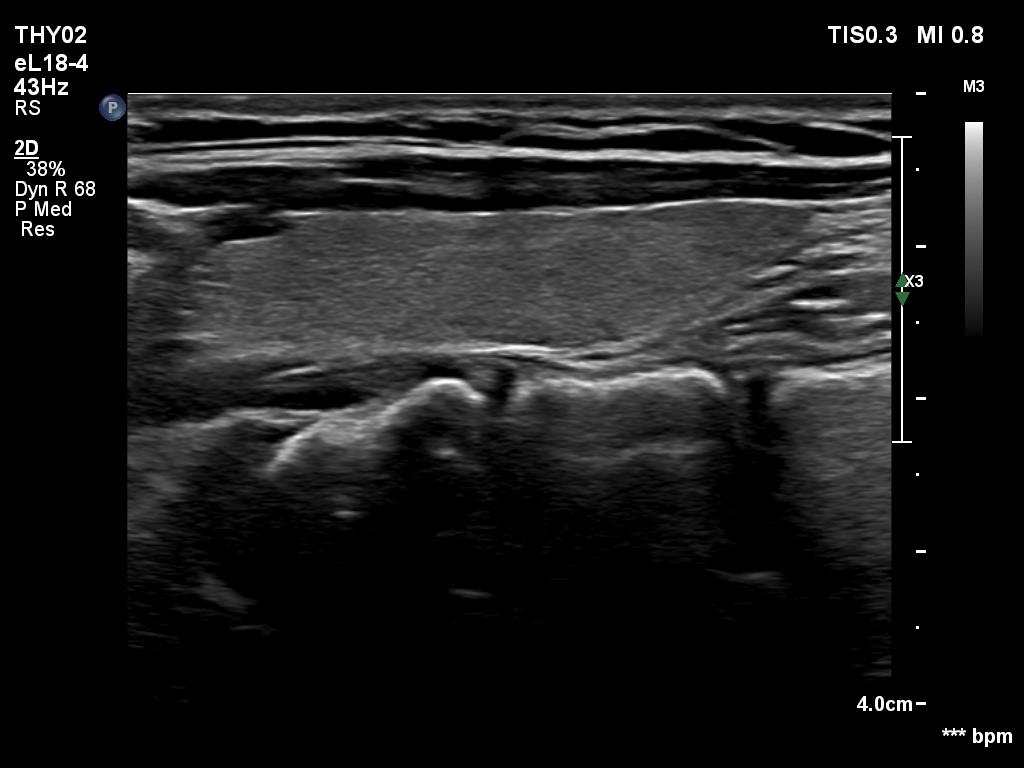

Elastography - case 1703 (ultrasonographic picture 7)

Left lobe, longitudinal view.